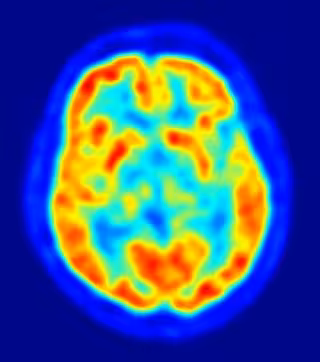

La reparación en el nivel celular del hipotálamo - una región crítica y compleja del cerebro que regula fenómenos como el hambre, el metabolismo, la temperatura corporal y comportamientos básicos, como el sexo y la agresión - indica la posibilidad de nuevos enfoques terapéuticos para condiciones de mayor nivel como la lesión de médula espinal, el autismo, la epilepsia, la esclerosis lateral amiotrófica (enfermedad de Lou Gehrig), la enfermedad de Parkinson y la enfermedad de Huntington.

"Sólo hay dos áreas del cerebro conocidas que se someten normalmente al reemplazo neuronal durante la edad adulta a nivel celular - la llamada neurogénesis, o nacimiento de nuevas neuronas - el bulbo olfativo y una subregión del hipocampo llamada circunvolución dentada", explica Jeffrey Macklis, profesor de Biología Regenerativa en Harvard, quien añade que "las neuronas que se añaden durante la edad adulta en ambas regiones son generalmente pequeñas, y se cree que actúan como los controles de volumen de la señalización específica. En nuestro nuevo estudio hemos reconectado circuitos cerebrales dañados que no experimentan naturalmente la neurogénesis, y hemos conseguido restaurar su función normal".

Para trasplantar las células exactamente en la región correcta y microscópica del hipotálamo, los científicos utilizaron una técnica llamada microscopía de alta resolución por ultrasonidos. Las neuronas sobrevivieron al proceso de trasplante y se desarrollaron estructural, molecular y electrofisiológicamente; además estas nuevas neuronas se integraron funcionalmente en los circuitos, respondiendo a insulina, la leptina, y la glucosa.